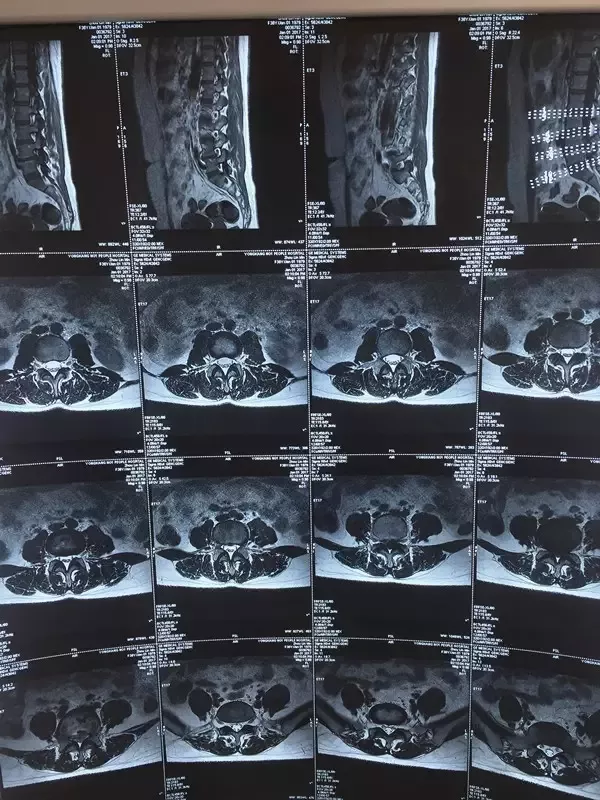

周女士今年剛滿40歲,卻有著10多年的腰腿痛病史,真正嚴重影響到正常生活是在2015年10月學車以后。2015年12月就診于縉云縣鈄氏傷科醫院行腰椎MRI檢查示:腰4-5椎間盤突出,確診為“腰椎間盤突出癥”,由于“突出”太大,建議其手術治療。但由于擔心手術風險,一直尋求保守治療,這一年多來周女士去過大大小小的醫院、診所,嘗試過各種膏藥、針灸、針刀、口服中藥等保守治療,病情一直未見好轉。

(圖為:患者的核磁共振片子)

2016年12月,周女士無明顯誘因下再次出現疼痛加重。經人介紹找到了我,她當時表情痛苦,步態跛行,表現出強烈的腰和右下肢的疼痛、麻木,交流過程中發現她站、坐、臥都找不到緩解疼痛的姿勢,由于癥狀較前嚴重,我建議她重新復查腰椎MRI。